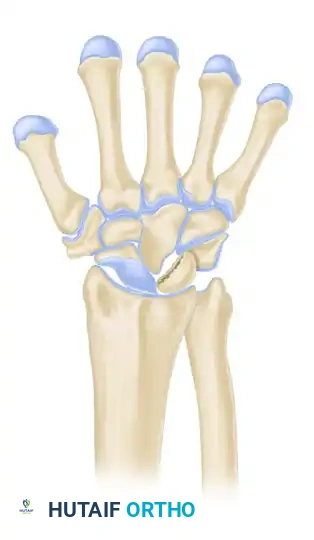

Armistead et al., utilizing CT imaging, demonstrated that occult fractures of the lunate are present in a significant subset of Kienböck patients.

A common fracture pattern is the anterior pole type, which isolates the anterior pole from the remaining bone. The compressive force exerted by the capitate distracts the fracture, diminishing the likelihood of healing. As the dorsal portion of the lunate collapses, the anterior pole may be extruded volarly. Furthermore, the ratio of carpal height to the length of the third metacarpal is reduced (normal is 0.54 ± 0.03), indicating overall carpal collapse.

LICHTMAN CLASSIFICATION OF KIENBÖCK DISEASE

The staging classification proposed by Lichtman et al. is the universally accepted framework for guiding surgical decision-making. The natural history, if left untreated, progresses from sclerosis to fragmentation, carpal collapse, and ultimately pancarpal arthritis.

Stage IIIA

- Description: Fragmentation and collapse of the lunate occur, but carpal alignment is maintained. The scaphoid remains normally aligned.